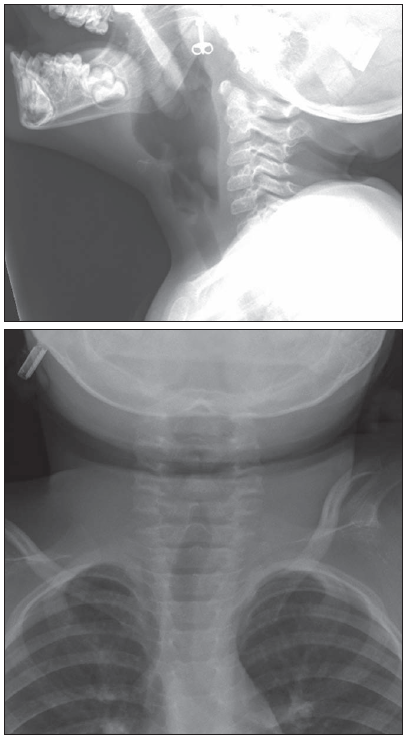

You order frontal and lateral views of the patient's airway.

On the lateral view (Figure 1a), you can determine the degree of head tilt and rotation by checking how well the angles of the 2 mandibles line up with each other. The mildly misaligned mandibles in this film indicate that the patient's head is slightly tilted; however, the degree of tilt is within acceptable bounds. In addition, the vertebral bodies and corresponding posterior elements appear well aligned. The study was performed in the inspiratory phase; thus, the oropharynx, nasopharynx, hypopharynx, larynx, and trachea are all well visualized.

On the frontal view (Figure 1b), the positioning of the child is also satisfactory. The region in question is adequately visualized. The glottis is closed.

Neither view is marred by motion artifact. It is preferable to remove articles of jewelry before a radiographic study, but the small earring visible in the lateral view will not inhibit assessment or formulation of a treatment plan.